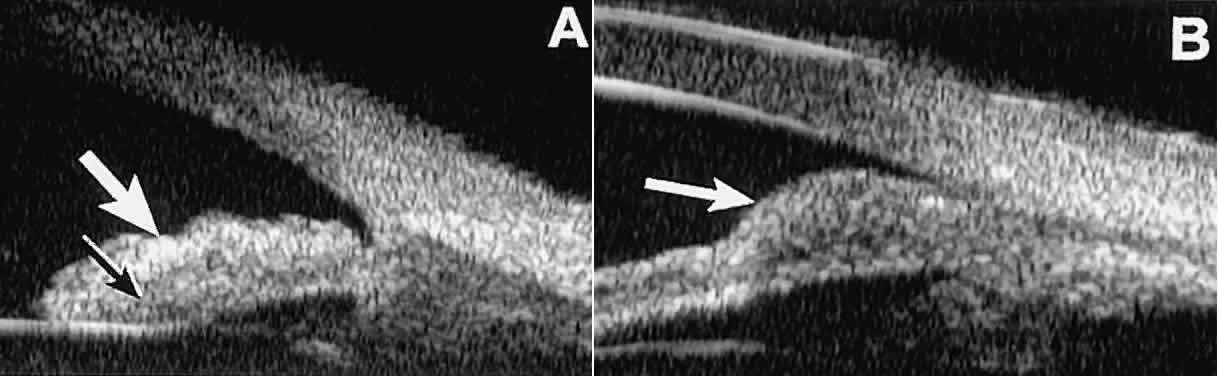

Solid iridociliary tumors present variable internal reflectivity depending on tumor type.14 Most solid lesions that occur on the iris are nevi. Benign nevi of the iris and ciliary body usually appear on UBM as relatively small hyporeflective lesions replacing a part or all of the underlying uveal stroma locally (Fig. 26). Such lesions usually do not destroy the underlying neuroepithelium of the iris or ciliary body, extend intrasclerally, or have prominent intralesional blood vessels.

Fig. 26. UBM features of iris nevi. A. Superficial nevus appears as hyper-reflective layer of iris (white arrow). Normal iris stroma (dark arrow) is more sonolucent. B. Fusiform nevus of peripheral iris occupying full thickness of iris stroma (arrow). Note intact iris pigment epithelium underlying lesion.

In contrast, malignant melanomas of the iris and ciliary body are much less common. On UBM, such tumors are usually larger than benign nevi, and they are more likely to have caused focal or extensive disruption of the adjacent neuroepithelial layers, to have invaded the sclera, and to be associated with prominent intralesional blood vessels (Fig. 27). Some malignant melanomas of the ciliary body and most ciliochoroidal melanomas are too large in basal diameter to be fully revealed in a single UBM image, and many of these lesions are also too thick to be measured by this technology. In the case of a melanocytic tumor of the iris or ciliary body that is not clearly either a benign nevus or a malignant melanoma, serial UBM evaluations may prove useful for assessing the tumor's growth and other changes that might warrant either biopsy or complete excision of the mass.

Fig. 27. UBM features of malignant melanoma of iris. (A) Iridociliary melanoma replacing peripheral iris and ciliary body and filling anterior chamber angle. Mass is slightly sonolucent compared with normal iris stroma. (B) Larger iridociliary melanoma. Iris appears to arise from side of mass.